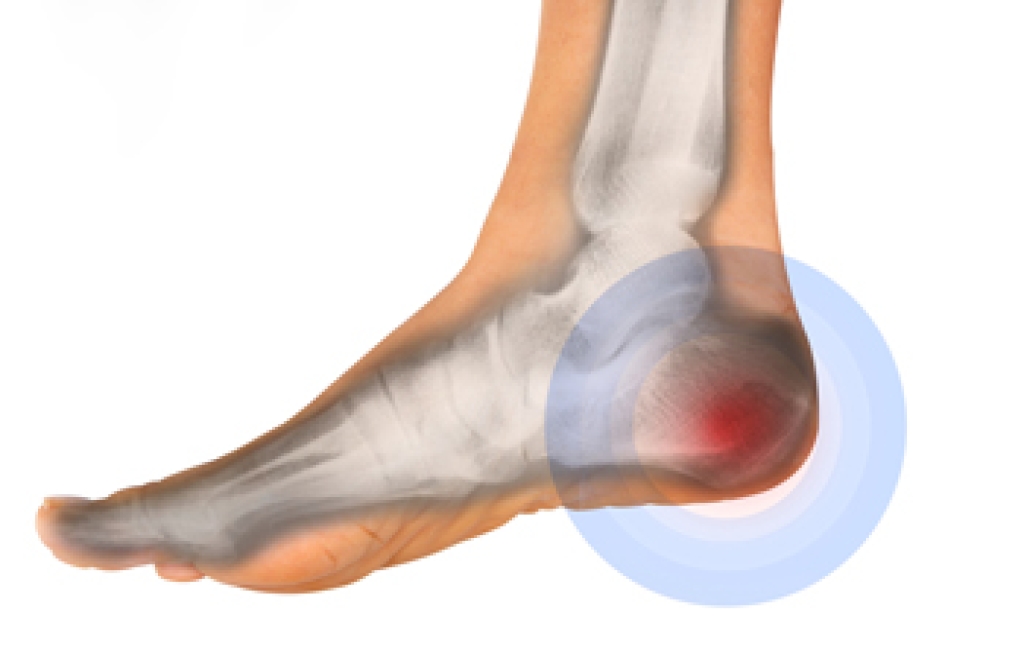

A small growth on the bottom of the heel bone may indicate a heel spur. Patients who have plantar fasciitis may have heel spurs, and this affects the tendon that runs along the bottom of the foot. People who are afflicted with heel spurs often notice heel pain after arising in the morning, and mild relief may be found while walking. The pain may become worse if running or participating in sporting activities, and it is beneficial to rest and elevate the affected foot. It may be helpful to take anti-inflammatory medications which may partially reduce existing pain. If you have the symptoms of a heel spur, it is strongly suggested that you speak to a podiatrist who can recommend the correct treatment options for you, which may include custom-made orthotics.

Heel spurs are formed by calcium deposits on the back of the foot where the heel is. This can also be caused by small fragments of bone breaking off one section of the foot, attaching onto the back of the foot. Heel spurs can also be bone growth on the back of the foot and may grow in the direction of the arch of the foot.

The pain associated with spurs is often because of weight placed on the feet. When someone is walking, their entire weight is concentrated on the feet. Bone spurs then have the tendency to affect other bones and tissues around the foot. As the pain continues, the feet will become tender and sensitive over time.